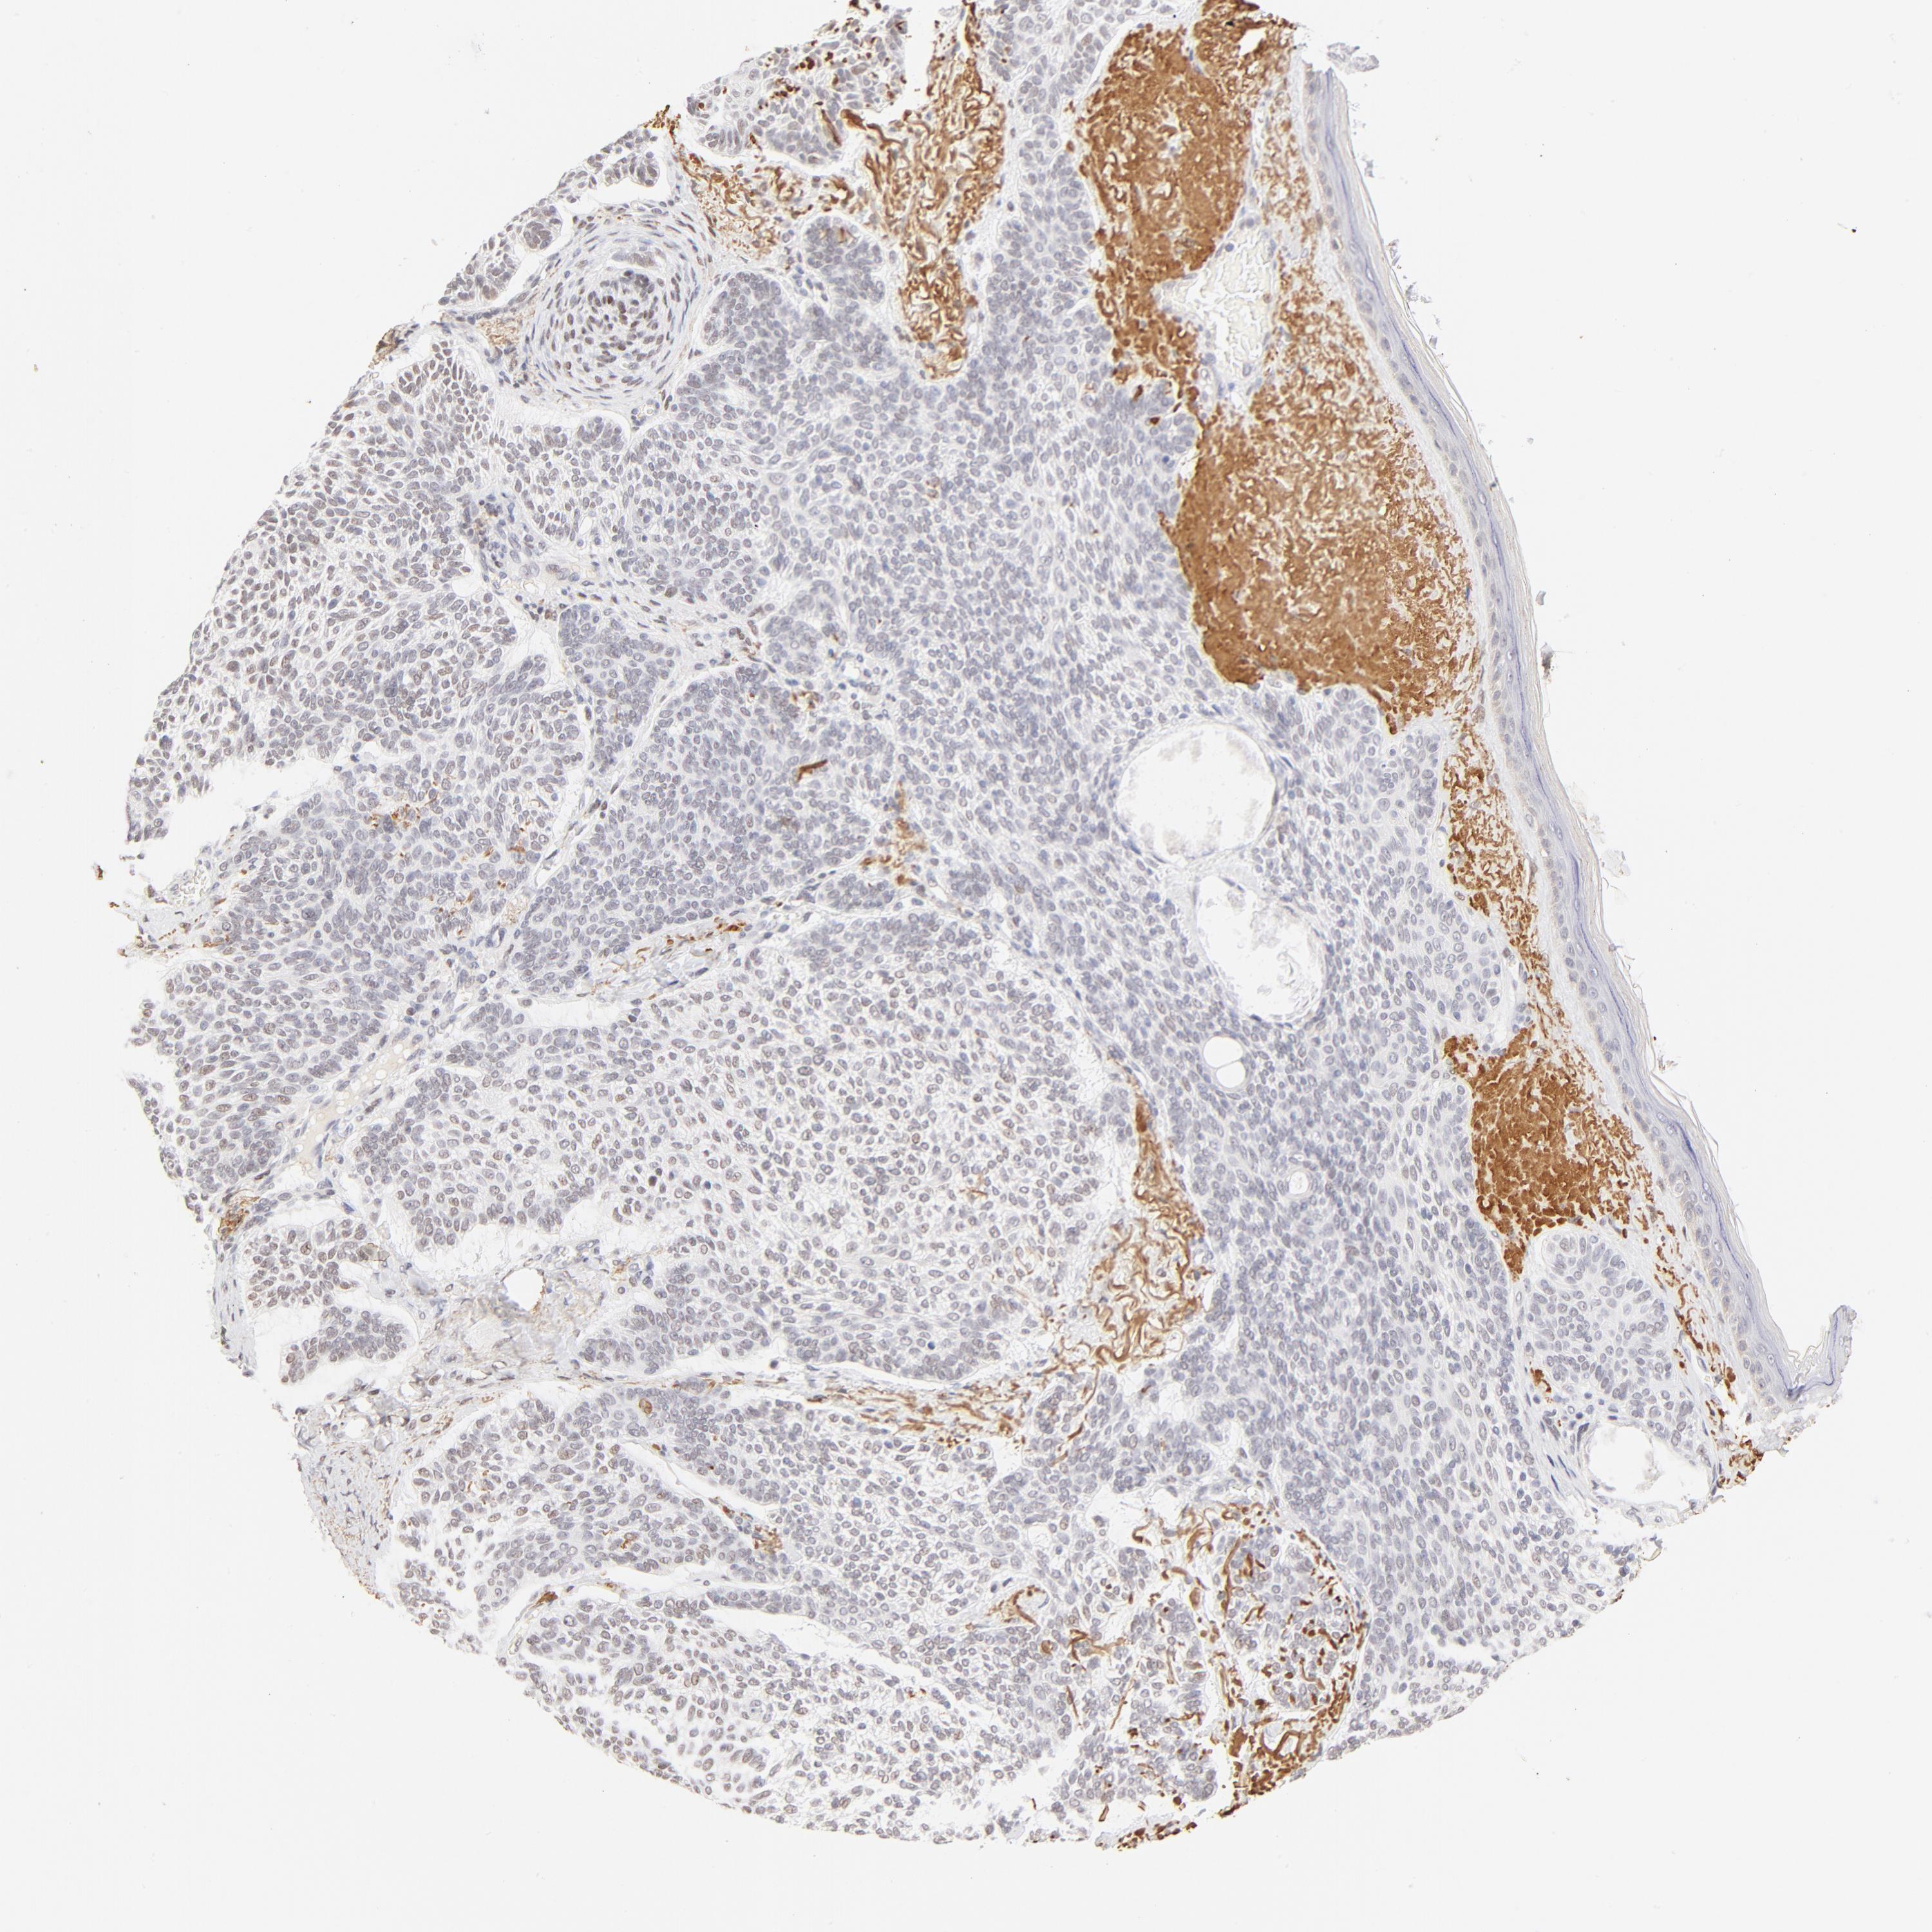

CANCER SKIN CANCER Show tissue menu

Basal cell and squamous cell cancer

SKIN CANCER - Protein expressioni

A mouse-over function shows sample information and annotation data. Click on an image to view it in a full screen mode. Samples can be filtered based on level of antibody staining by selecting one or several of the following categories: high, medium, low and not detected. The assay and annotation is described here.

Antibody stainingi

Antibody staining in the annotated cell types in the current human tissue is reported as not detected, low, medium, or high, based on conventional immunohistochemistry profiling in selected tissues. This score is based on the combination of the staining intensity and fraction of stained cells.

Each image is clickable and will lead to virtual microscopy that enables deeper exploration of all samples and also displays staining intensity scores, fraction scores and subcellular localization as well as patient and tissue information for each sample.

Antibody HPA003505

Antibody HPA003881

Antibody CAB018768

Staining

High

Medium

Low

Not detected

Intensity

Strong

Moderate

Weak

Negative

Quantity

>75%

75%-25%

<25%

None

Location

Nuclear

Cytoplasmic/membranous

Cytoplasmic/membranous,nuclear

Squamous cell carcinoma, NOS

Basal cell carcinoma

Squamous cell carcinoma in situ, NOS

Squamous cell carcinoma, metastatic, NOS